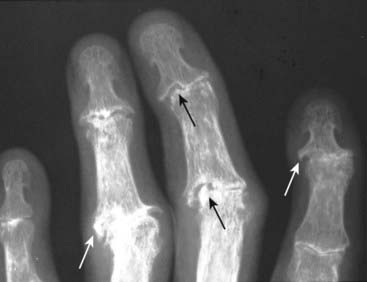

Figure 23-18 Psoriatic arthritis, hand (A) and foot (B).

A, Psoriatic arthritis typically involves the small joints of the hands, especially the distal interphalangeal (DIP) joints (solid white arrows) leading to telescoping of one phalanx into another (pencil-in-cup deformity). B, In the foot of another patient with psoriasis, there is ankylosis of the 2nd toe (solid black arrow) and more pencil-in-cup deformities (dotted white arrows).